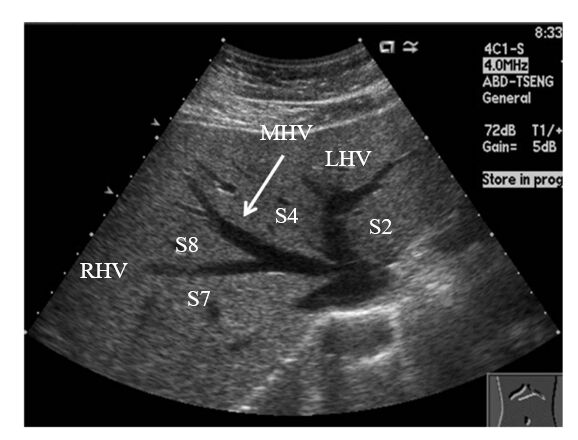

62.肝臟超音波橫向掃描時,發現一個高回音性病灶,介於右肝靜脈(right hepatic vein, RHV)與中肝靜脈(middle hepatic vein, MHV)之間(如下圖)。根據Couinaud classification的分 類,此病灶應在肝臟的那一個節段(segment)?

圖中的三叉是由三條血管右肝靜脈(right hepatic vein, RHV)、中肝靜脈(middle hapatic vein, MHV)、左肝靜脈(left hepatic vein, LHV)構成,這三條血管可以把肝臟分成四葉,從右至左分別為S7、S8、S4、S2

此題考RHV和MHV中間夾的是哪一葉,從三叉的圖像可以得知,就是S8 -->(A) 8(VIII)